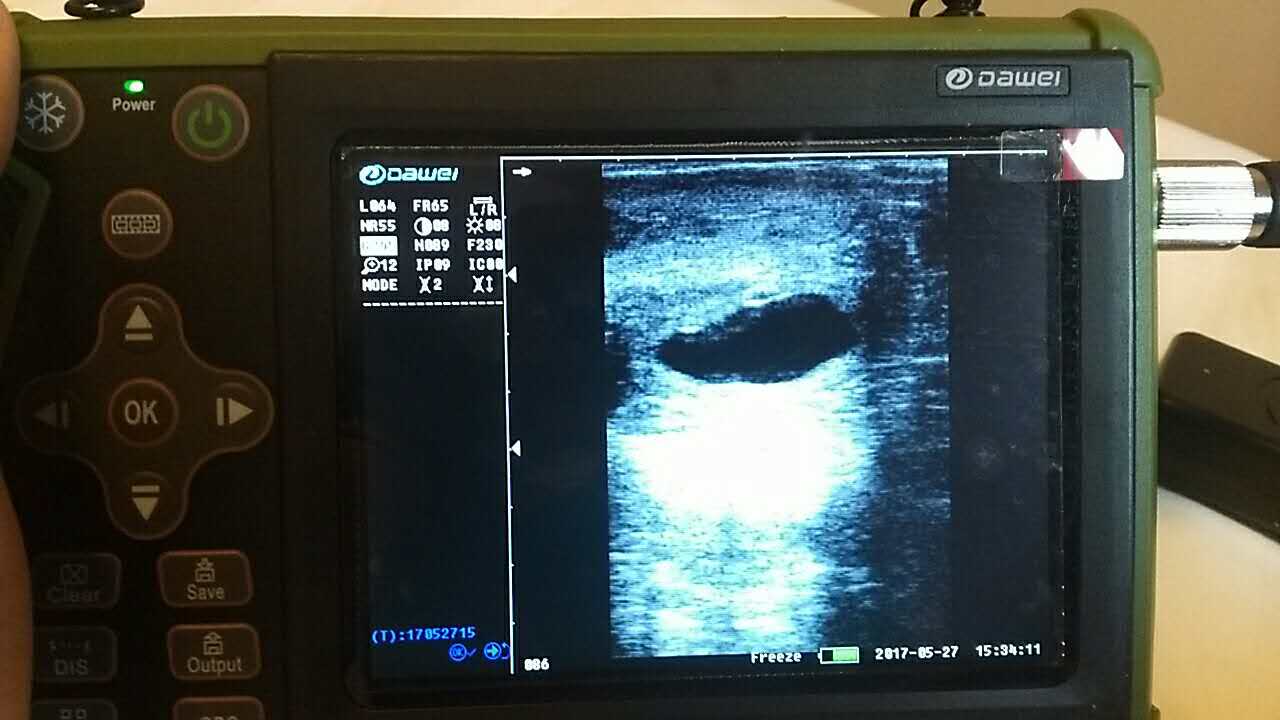

動物獸用B超機普通情況下死機情況分析

動物B超機使用售后反饋情況中,可以看到好多情況是普通的獸用B超死機的情況,這種普通情況下死機是如何產生的呢?大多數情況是在平時使用時候,由于各種設備和非設備問題導致,機器不能正常運轉。大為獸用B超經過對這些反應的情況,看到在所有動物B超設備的“死機”故障中,有很多情況如同計算機常碰到的死機故障一樣,平常處理這類情況,可以通過關機,然后再開機,機器就會正常工作。但是有的時候,獸用B超死機現象無論通過什么常規應急手段是排除不了的,大為獸用B超告訴維修人員不可心急,應耐心細致的去查找“死機”故障形成的原因,從而排除“死機”故障。下面大為獸用超聲來為您介紹幾種死機現象如何處理。